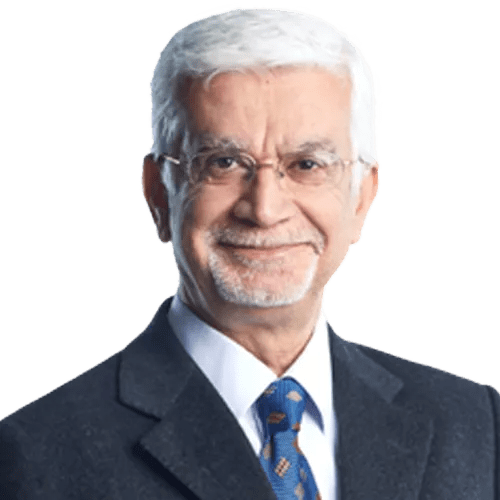

Çalışma, Environment International dergisinde yayımlandı ve İtalya’nın başkenti Roma’daki San Giovanni Calibita Fatebenefratelli Hastanesi’nde Doğum Bilim ve Jinekoloji Direktörü olan Antonio Ragusa tarafından yönetildi. Çalışmada 6 plasentanın incelendiği ifade edilirken, mikroplastik parçacıkları, normal gebelik ve doğumları olan 4 sağlıklı kadından alınan plasentaların hem fetüs hem anne tarafında hem de fetüsün geliştiği zarın içinde tespit edildi. Ayrıca, bir düzine plastik parçacıklarının bulunduğu, her plasentanın sadece yüzde 4'ünün analiz edildiği bunun da toplam mikroplastik sayısının çok daha yüksek olduğuna işaret ettiği ifade edildi. Analiz edilen tüm parçacıkların mavi, kırmızı, turuncu veya pembeye boyanmış plastikler olduğu ve parçacıkların kaynağının ambalaj, boya, kozmetik veya kişisel bakım ürünleri olabileceği belirtildi. Araştırmacılar, çalışmadaki diğer 2 kadının plasentasında parçacıkların bulunmadığını bunun da farklı fizyolojik yapı, diyet veya yaşam tarzının sonucu olabileceğini ifade etti.

Çalışmayı yöneten Antonio Ragusa konuyla ilgili olarak “Bir Cyborg (biyolojik ve yapay kısımları olan varlıklara verilen isim) bebeğe sahip olmak gibi; artık sadece insan hücrelerinden oluşmuyor, biyolojik ve inorganik varlıkların bir karışımından oluşuyor” ifadelerini kullandı. Ragusa ayrıca bulguların anneleri şoke ettiğini de belirtti.